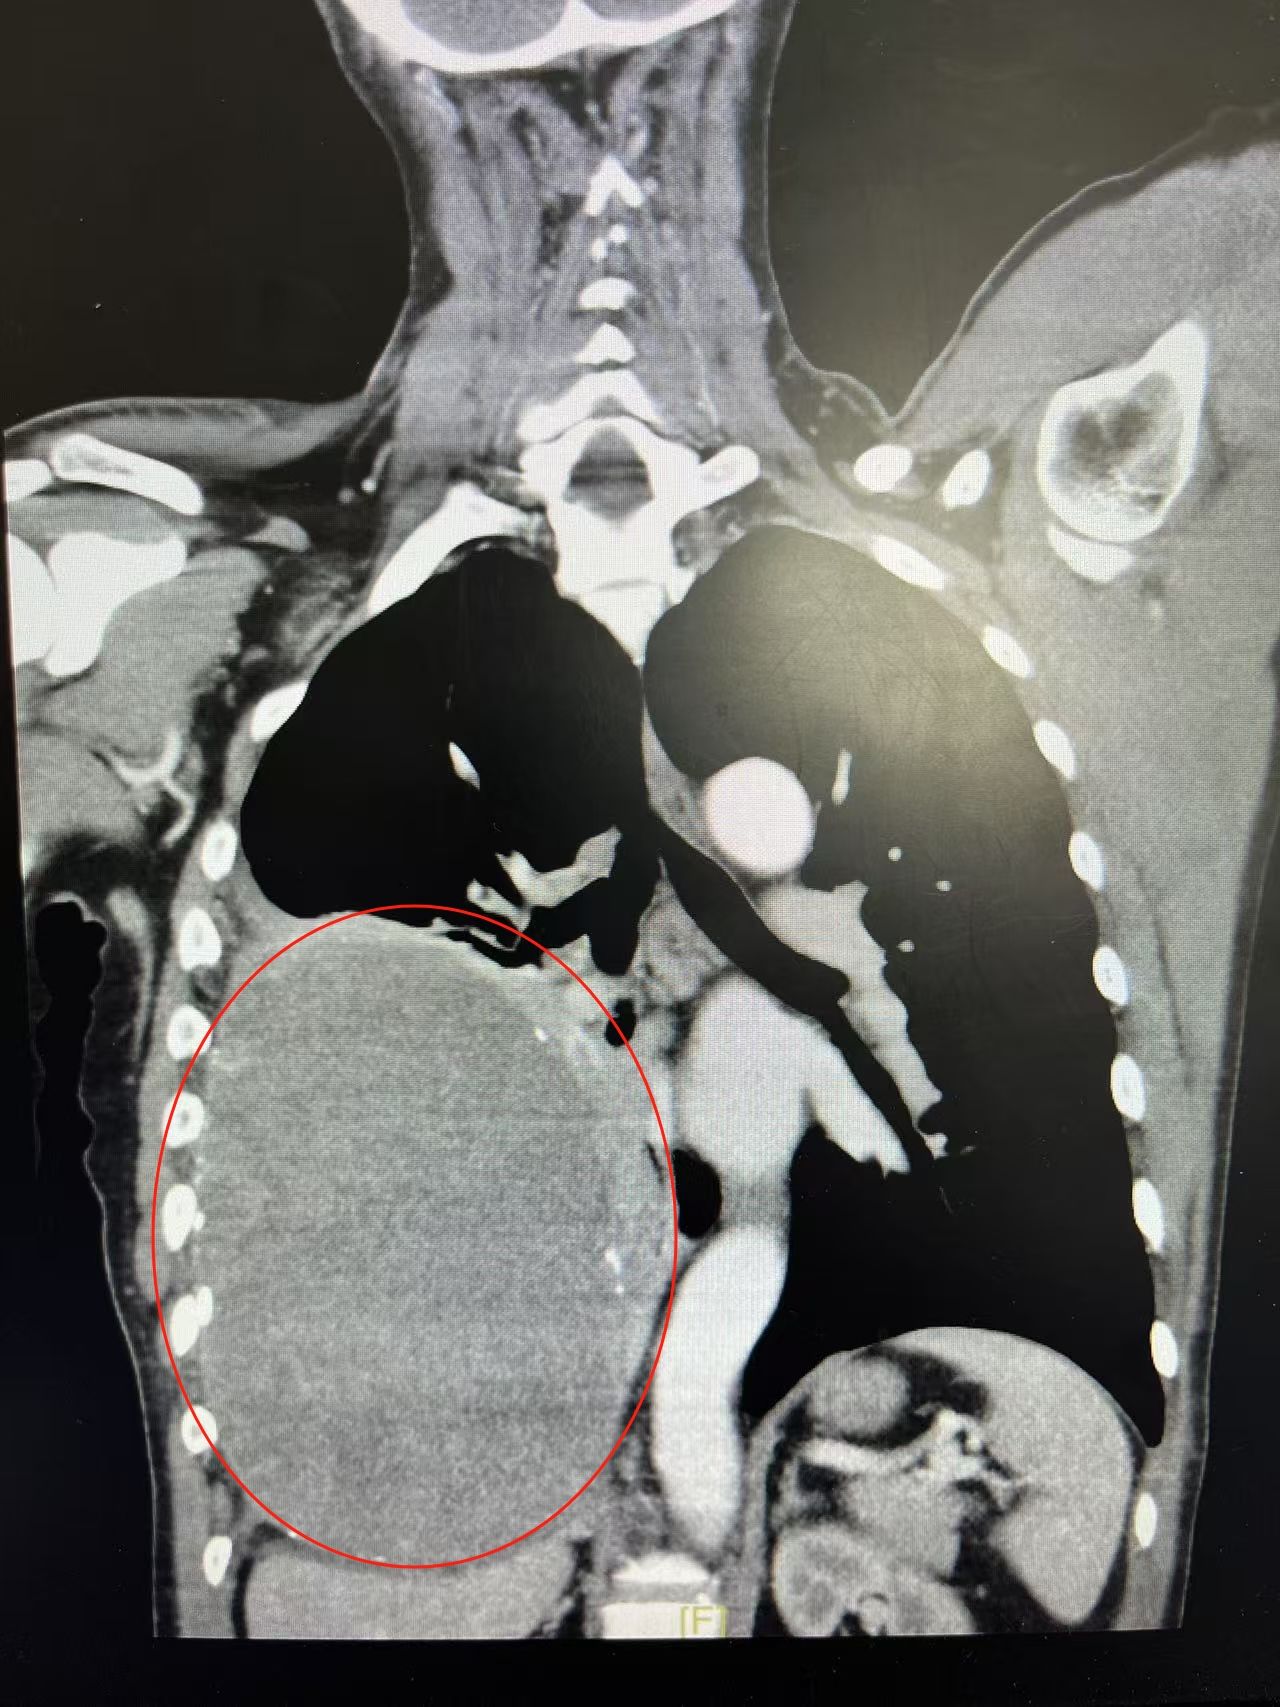

粤黔医联体协作,跨越1500公里胸腔拆弹